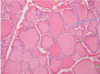

What gland is shown here

Parathyroid gland

Label this diagram of a parathyroid gland

- chief cells- purple, chief (more of them)

- Oxyphill cells- red/pink

What is secreted by the parathyroid gland, from which cell & what is its function

Chief cells- secrete parathyroid hormone

- -* plays a key role in the regulation of calcium levels in the blood; removes calcium from bones, to enter the blood

- What cells does this hormone act upon and what is their subsequent action? Cells of the bone & the kidney-* removes calcium from bones, to enter the blood

Parathyroid hormone takes calcium from bones, putting it into the blood

Calcitonin takes calcium from the blood and puts it into the bones

Complete the labels

Parathyroid hormone

A= Fibrous capsule

B= Adipose tissue

C= chief cells (purple)

D= Oxyphill cells